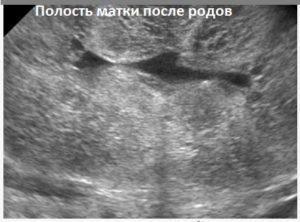

Посредством ультразвука оценивают полость матки, ее состояние. Она должна быть щелевидной, слегка расширенной. Внутри нее находится незначительное количество крови, кровяных сгустков, которые локализируются в верхней части органа. Это содержимое опуститься к низу на 5-е – 7-е сутки.

Отдельно оценивают состояние полости матки. В норме на 2–3-е сутки она должна быть щелевидной или незначительно расширена за счет небольшого количества крови, которая находится в верхней ее части. Смещение кровяных сгустков в нижние отделы происходит на 5–7-е сутки.